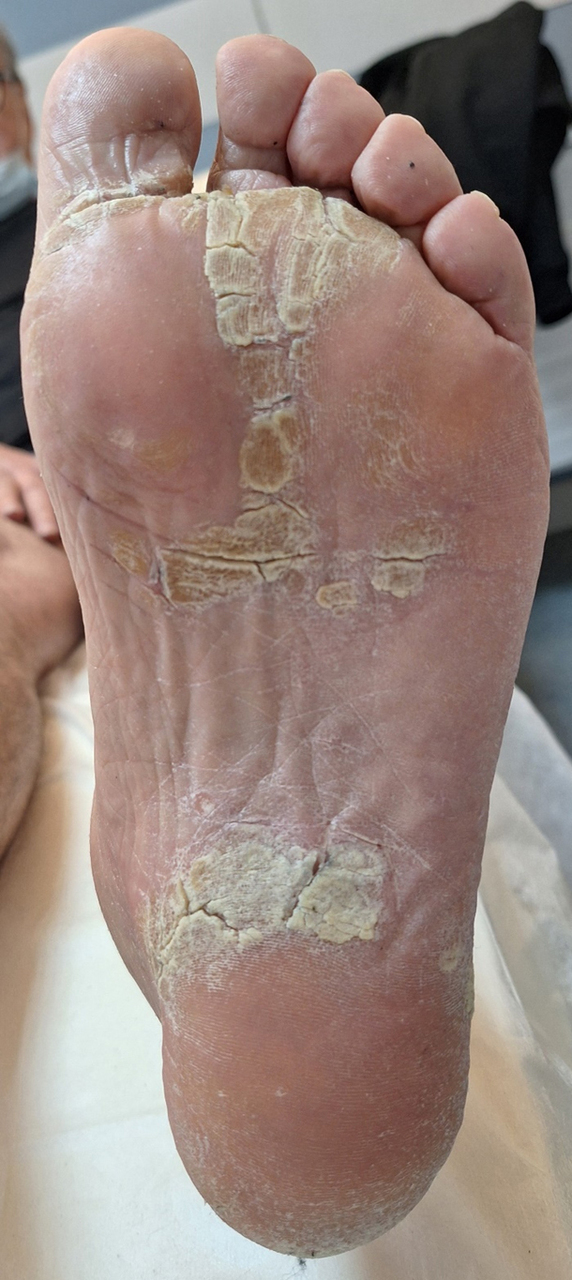

M. G. est suivi pour une hypertension artérielle, une dyslipidémie et un antécédent d’ulcère gastrique. Il a été opéré d’une hernie inguinale droite il y a cinq ans, et a subi une appendicectomie et une amygdalectomie dans l’enfance. Il n’y a pas d’antécédent familial notable. Son traitement est le suivant : amlodipine 10 mg/j, ramipril 5 mg/j, atorvastatine 40 mg/j, lansoprazole 30 mg/j. Il ne fume pas et boit 2 verres de vin par jour. Il ne décrit pas de signe associé notamment pas d’altération de l’état général, pas de fièvre, pas de rachialgie, pas de trouble digestif, pas d’antécédent ophtalmologique. Vous complétez votre examen clinique. Les paramètres vitaux sont les suivants : pression artérielle (PA) = 141/86 mmHg ; fréquence cardiaque (FC) = 76/min ; température (T°) = 36,7 °C ; saturation en oxygène (SpO2) = 99 %. L’auscultation cardiopulmonaire et la palpation abdominale sont sans particularité. L’examen cutané retrouve l’aspect suivant : Figure 1 (Source : Salomé Abdellaoui, La Revue du Praticien)

La lésion élémentaire est une squame.

Le psoriasis est la principale cause de kératodermie palmoplantaire à connaître pour l’EDN.

La présentation oriente plutôt vers un psoriasis.

Dans le cadre d’une kératodermie palmoplantaire.

Le patient a une hyperkératose plantaire, ce qui peut s’intégrer dans le cadre d’un psoriasis, avec souvent une atteinte similaire des mains. Le diagnostic d’arthrite septique est peu probable : pas de fièvre, notion d’antécédent similaire résolutif après la prise d’anti-inflammatoires, association à un psoriasis qui rend le diagnostic de spondylarthropathie plus probable.